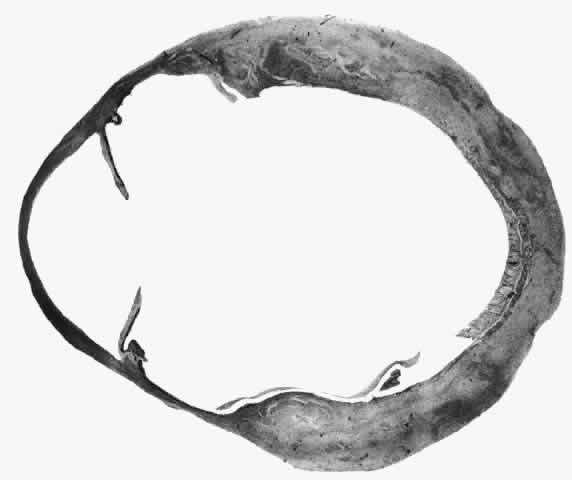

changes of scleral edema or necrosis. The onset of scleritis is usually gradual, building up over several days. By the time patients seek advice, the clinical types can be distinguished as anterior or posterior, or occasionally both. Anterior scleritis may be further subdivided into diffuse, nodular, or necrotizing. The last condition may present with signs of inflammation or with few or no signs of inflammation (scleromalacia perforans). Long-term follow-up of patients with scleral disease showed that only 8% of patients changed from one type of disease to another during the course of this disease, so although differentiation into these types does not usually indicate an etiology, it does have a direct bearing on the prognosis and the type of treatment to be used.10 Scleritis is most common in the fourth to sixth decades of life and occurs more frequently in women than men (8:5). Necrotizing scleritis occurs later than the other varieties, the mean age being 61 years. Scleritis is bilateral in 52% of patients. In half of these, the condition starts in both eyes simultaneously, with the rest becoming bilateral in 5 or more years. ASSOCIATED SYSTEMIC DISORDERS In a review of 1200 patients with scleritis who have attended the Scleritis Clinic at Moorfields Eye Hospital in London, an associated systemic disorder was found in all patients with scleromalacia perforans, in half of those with nodular and necrotizing disease, in a third of those with diffuse anterior scleritis, and in only 10% of those with posterior scleritis. Severe polyarticular rheumatoid arthritis and a case of porphyria accounted for the patients with scleromalacia perforans. Forty percent of the patients with necrotizing scleritis had other connective tissue disorders, but, surprisingly, only 21% of the patients with diffuse anterior or nodular scleritis had rheumatoid arthritis or other connective tissue disorders. This percentage is much lower than that reported by other authors,7,11–13 but this may be because patients with the less severe scleral disease are referred to us only if the etiology is in doubt, thus biasing the results. Twelve percent of the patients with diffuse anterior and nodular scleritis had ankylosing spondylitis, and in a further 15% the scleritis followed an attack of herpes zoster ophthalmicus. A variety of other conditions, including syphilis, tuberculosis, gout, Reiter's disease, IgA nephropathy, and erythema nodosum, were thought to be definite etiologic factors because with appropriate treatment the eye changes disappeared. Fowler investigated a random selection of the patients with scleritis at Moorfields Eye Hospital and found only 7%, all of whom were young males, who did not have any other detectable physical abnormality.14 Forty percent of these patients had hypertension, which in some cases required treatment. It was thought that the hypertension could have been a manifestation of a generalized arteritis, but this was convincingly demonstrated in only 19% of these patients. PATHOLOGY The pathology of scleritis has received much attention in the past.6,8,15–19 Although certain inferences can be drawn from pathologic specimens of eyes removed because of pain, perforation, or mistaken diagnosis, these eyes have been severely damaged from advanced disease. Unfortunately, biopsies of scleral lesions have proved to be unsatisfactory, at best yielding material of limited diagnostic value and at worst leaving an area of exposed choroid that will not heal. Consequently, they should not be performed. Scleritis usually affects the anterior segment of the eye, possibly because this is the area with the best blood supply, but with sluggish flow through the vessels (Fig. 19). The sclera is thickened and roughened in the affected area, which appears to be sharply demarcated from the rest of the sclera. However, tissue obtained at surgery during the course of grafting of areas adjacent to necrotic tissue shows marked pathologic changes.20,21 The area of affected sclera may be swollen, excavated, or frankly ulcerated with undermined edges covered with a thin layer of fibrous tissue. However, spontaneous perforation is extremely unusual and, where seen in pathologic specimens, has usually occurred at the time of removal of the eye. A posterior scleritis often occurs as an extension of anterior disease; but, as in Figure 20, most of the inflammation (in some cases all of the inflammation) is in the posterior segment and the exudative detachments and subretinal granulomas can be mistaken for malignant melanoma.

What is clinically represented solely by inflammation and edema is histopathologically a granulomatous lesion of the sclera, the center of which consists largely of plasma cells, lymphocytes, and mast cells (Figs. 21 through 23). Foster and colleagues have identified the cellular subsets and glycoproteins in both necrotizing and non-necrotizing scleritis.22 This shows an active T-cell inflammatory response with a high CD4/CD8 ratio and increased HLA/DR and CD14, indicating a macrophage-induced response that would lead to granuloma formation. Remote from the granuloma, the fibrocytes of the sclera become activated, the proteoglycan adjacent to them becomes altered, and the collagen fibrils of the sclera become unraveled (Figs. 23 and 24). These changes appear to take place prior to the invasion of the stroma by cells of the granuloma.20 The vessels in and around the necrotic area show medial necrosis and perivascular cuffing with lymphocytes, and endothelial swelling with microvascular occlusion. Ninety-six percent of the specimens examined by Foster and associates show a microangiopathy characterized by a neutrophil infiltrate in and around the vessel wall.22–23 This is most obvious at the center of the lesion where there may be occlusion of the vessel, thrombosis, or even aneurysm formation (Fig. 25). From these pathologic investigations, clinical observations, animal experiments, and the results of fluorescein angiography, it would appear that the scleral inflammation is initiated either by trauma (be it accidental or surgical)23–25 or by bacterial or viral infection. If circulating immune complexes are present because of the poor blood flow, they become precipitated in and around the vessel walls in the area of inflammation. In other patients, a persistence of tissue damage will lead to autoimmunization. Damage to the endothelial cells of the microvasculature leads to changes within the vessels detectable on angiography and to catabolic changes in the surrounding tissues. These changes, in turn, allow the granulomatous response that is seen in histopathologic sections, the first detectable change being in the scleral fibrocytes and the proteoglycan and collagen remote from the site of cellular infiltration.